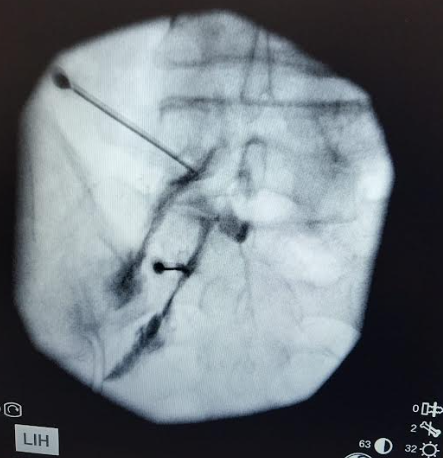

Bloquejos espinals

Un procediment mínimament invasiu que se centra en nervis espinals específics per alleujar el dolor causat per la inflamació o la irritació nerviosa, proporcionant alleujament.